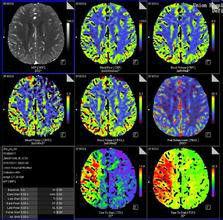

CT灌注CBF、CBV、MTT圖西門子公司使用斜率法計算得出血容量(BV )至峰值時間(TTP )以及瞬間最大密度投影(tMIP )函式圖。BV 從組織增強峰值與動脈增強峰值的比率中計算出來。飛利浦公司 C T 灌注軟體也使用斜率法計算函式, 但使用Mullani~Gould 公式計算瞬間最大密度投影(tMIP)圖像、峰值增強圖像、TTP 、MTT 的函式圖。先在動脈內放置一個感興趣區,得到一條光滑的動脈增強曲線,以此來確定至峰值時間。G E 公司使用去卷積算法,對動態圖像數據進行分析,獲得 BF 、BV 、MTT 、PS 等灌注參數及函式圖。2001 年,該公司把多層技術與CT 灌注成像相結合研製開發了新的軟體包,實現了多層同層動態CT 灌注掃描,即“Toggling-Table”技術 ,克服了單層螺鏇 CT 的 Z軸掃描範圍小的缺點,可實現多層同時掃描,增大了檢查的縱向解剖範圍,能夠挑選病變截面較大、靜脈清楚、圖像質量好的一組進行分析,使得到的灌注參數更加準確。